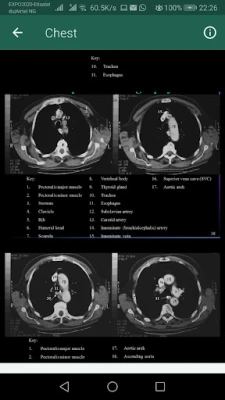

Το "Sectional Anatomy for Imaging Professionals, the App" αποτελεί τον απαραίτητο ψηφιακό σύμμαχο για κάθε επαγγελματία και σπουδαστή απεικονιστικών μεθόδων. Σχεδιασμένο για να προσφέρει μια ασυναγώνιστη οπτική εμπειρία, η εφαρμογή μετατρέπει την περίπλοκη ανατομία σε κατανοητή γνώση. Μέσα από μια καινοτόμο προσέγγιση, παρουσιάζει πλάι-πλάι πραγματικές διαγνωστικές εικόνες από μαγνητικές τομογραφίες (MRI) και αξονικές τομογραφίες (CT), μαζί με λεπτομερή ανατομικά σχέδια, φωτίζοντας τις πιο συχνά απεικονιζόμενες ανατομικές δομές του σώματος.

Με μια εκτενή συλλογή που ξεπερνά τις 1.500 εικόνες υψηλής ανάλυσης, συμπεριλαμβανομένων αυθεντικών απεικονίσεων και καθαρών γραμμικών σχεδίων, το "Sectional Anatomy for Imaging Professionals, the App" καλύπτει κάθε ανατομικό επίπεδο που συναντάται στην κλινική πράξη. Η παράλληλη απεικόνιση εικόνων και σχεδίων προσφέρει άμεση σύγκριση, ενισχύοντας την κατανόηση της θέσης και της λειτουργίας κάθε δομής. Κάθε ενότητα περιλαμβάνει σαφείς περιγραφές και ευδιάκριτες ετικέτες, επιτρέποντας την άμεση και ακριβή αναγνώριση των ανατομικών σημείων κατά τις εξετάσεις.

Αποτελώντας ένα ολοκληρωμένο βοήθημα αναφοράς, η εφαρμογή ενισχύει την ικανότητά σας να παράγετε διαγνωστικές εικόνες υψηλότερης δυνατής ποιότητας. Οι ενημερωμένοι πίνακες σύνοψης απλοποιούν την οργάνωση βασικών πληροφοριών, ενώ ειδικές εικόνες στην έναρξη κάθε κεφαλαίου κεντρίζουν το ενδιαφέρον για την επερχόμενη ύλη. Αναφορά σχέδια και αντίστοιχα επίπεδα σάρωσης εμφανίζονται δίπλα στις πραγματικές εικόνες, προσφέροντας εύκολη συσχέτιση. Να σημειωθεί ότι το "Sectional Anatomy for Imaging Professionals, the App" είναι ένα εκπαιδευτικό και αναφοράς εργαλείο, και όχι συσκευή αξονικής ή μαγνητικής τομογραφίας.